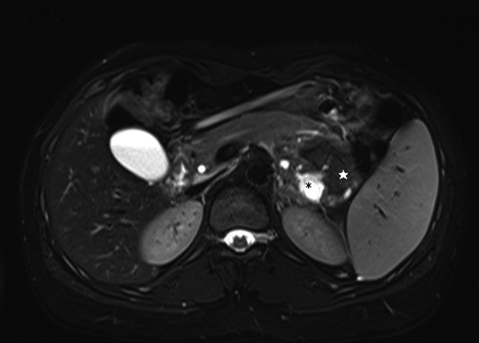

腹部造影MRI所見:腫瘤は膵臓との境界が不明瞭で,内部はT1強調像で高信号,T2強調像で低信号を呈していた.内部の造影効果は認めなかった.腫瘤内にはT1強調像で低信号,T2強調像で高信号を呈するcyst in cyst様の多房状構造,隔壁様構造を認めた(Fig. 2).

Abdominal MRI scan showing a small septated cyst that appears hyperintense on T1- and hypointense on T2-weighted imaging (asterisk).